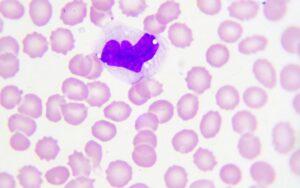

Monocitos